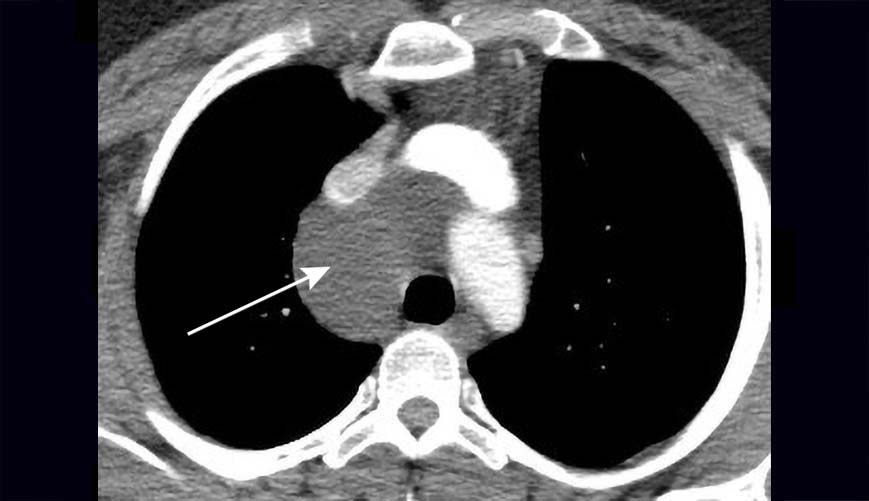

Computed tomography image illustrating many bilateral lung cysts of

Figure 1 from Characteristic CT appearance of lung cysts prompting the